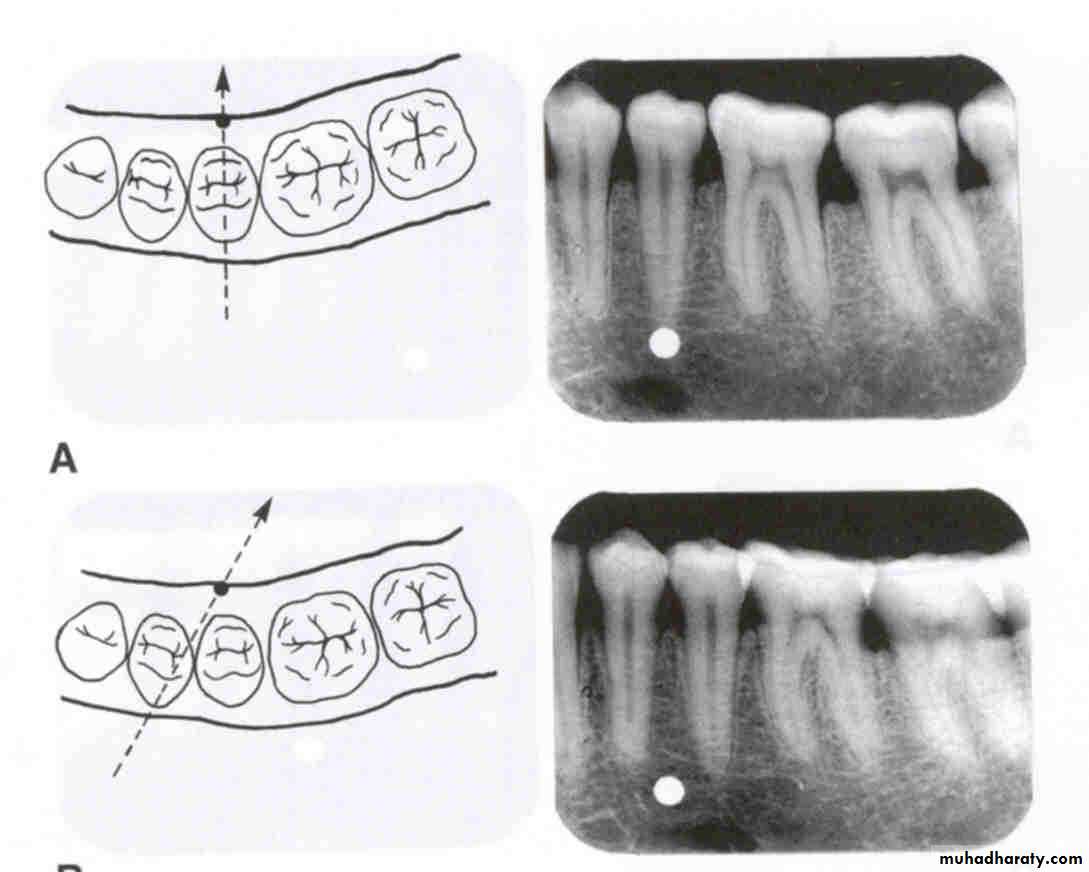

Vertical movement of the tube head and x-ray beam

In moving from the maxillary periapical to the bitewing and from the bitewing to the mandibular periapical, the tube head moves down and the beam is redirected upward (opposite direction; decreased vertical angulation).

Vertical movement

In the diagram at left, the tube head is moved upward and the beam is directed downward. On the radiograph, the buccal object of interest (yellow) moves down (opposite to tube head movement) in relation to the second premolar and the lingual object of interest (red) moves up (same direction as tube head) in relation to the second premolar.

In the diagram at left, the tube head is moved downward and the beam is directed upward. On the radiograph, the buccal object of interest (yellow) moves up (opposite to tube head movement) in relation to the second premolar and the lingual object of interest (red) moves down (same direction as tube head) in relation to the second premolar.